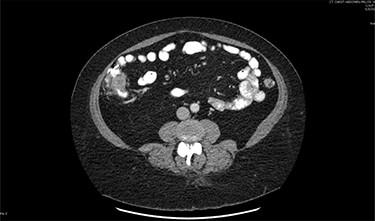

On assessment, the patient denied any symptoms related to her neuroendocrine tumor, including flushing, increased sweating, increased heart rate, wheezing, shortness of breath, diarrhea, weight loss or appetite changes. The only significant family history was a paternal and maternal grandfather with colon cancer. Imaging results were significant for computed tomography (CT) of chest demonstrating very small, but multiple, pulmonary nodules. A CT abdomen and pelvis demonstrated the known neuroendocrine tumor near the ileocecal valve (Fig. 1) as well as two poorly visualized liver lesions (Figs 2–4). The magnetic resonance imaging (MRI) demonstrated two separate one-centimeter lesions in segment 5 and 7 of the liver (Figs 5 and 6). The portal vein lacked normal left and right bifurcation; there was a circumferential right portal vein, which coursed anteriorly and superiorly and ultimately to the left lobe of the liver.

MRI image again demonstrating segment 5 metastatic lesion in close proximity to portal vein.